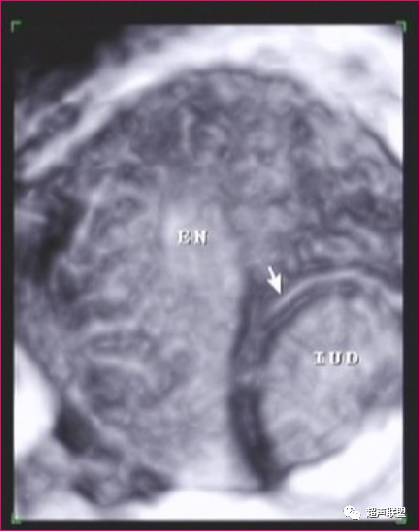

IUD合并妊娠

在子宫内显示妊娠囊与IUD的回声同时存在,可诊断为IUD合并宫内妊娠(带器妊娠)。超声诊断带器妊娠的价值在于能清晰的显示子宫、IUD和妊娠囊,以及三者的关系。

声像图特征:

1、子宫增大,增大的径值与孕周成正比。

2、早期妊娠时,在子宫腔内显示完整的妊娠囊,随妊娠周数的增加,囊内可见到胎芽、原始心管搏动及胎动。在妊娠囊的下方、侧方、上方或接近子宫颈口处,显示强回声的IUD,由于妊娠囊暗区的衬托,IUD回声显示格外清楚。